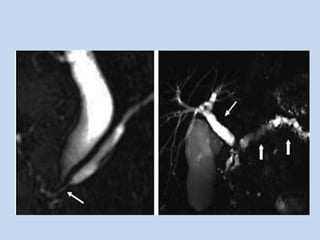

• In Choledocholithiasis :

- On MRCP stones appear as signal void in the

background of high signal intensity bile.

- number, size & location are determined.

- stones as small as 2mm can be identified with current

• In Primary Sclerosing Cholangitis :

- MRCP depicts the subtle ductal abnormalities that

characterize PSC – mural irregularities, strictures

& diverticular outpouchings.

- Conventional abdominal MR + MRCP provides

useful information regarding the presence of cirrhosis

& portal hypertension in PSC patients.